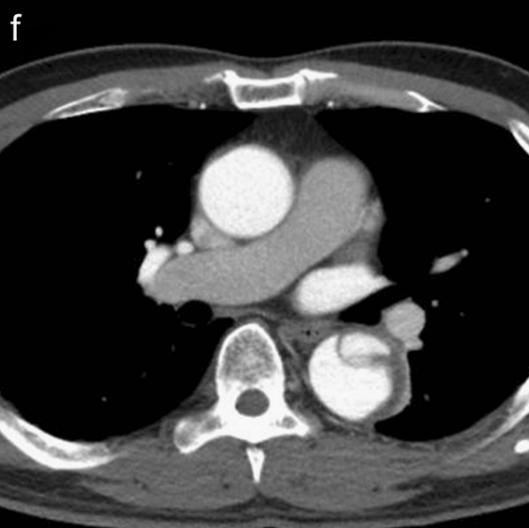

下图的胸部CT平扫,基本上大约肯定可以看到一条线样阴影,将主动脉一分为二!

图10

增强CT一看,主动脉裂开了!

图11